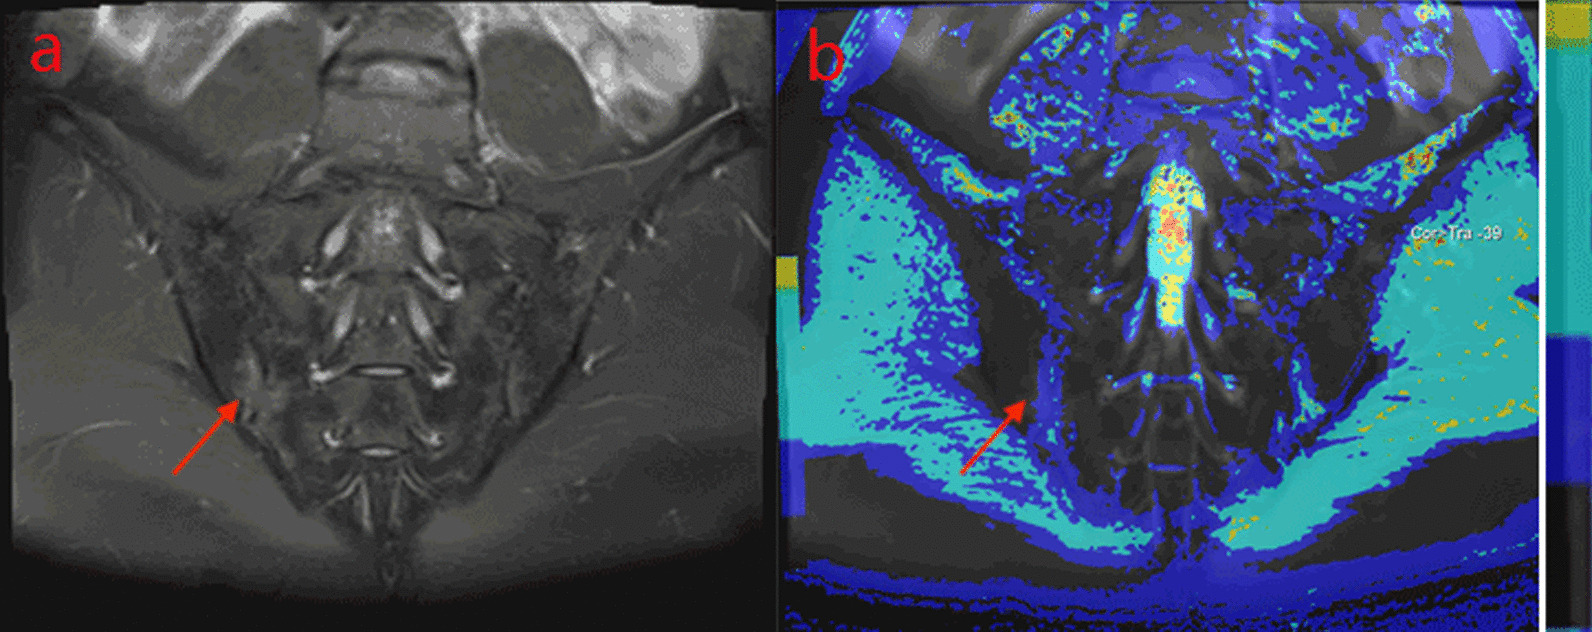

Fig. 1.

A male, 32 years old, HLA-B27: + , ASDAS-CRP:1.9, belongs to the moderate activity group. a The coronal plane of PDWI shows high signal intensity of bone marrow under right sacroiliac articular surface. b T1-mapping pseudo-color diagram demonstrates the T1-mapping values of regions of interest is 519.27 ms

Fig. 2.

A male, 27 years old, HLA-B27: ± , ASDAS-CRP:2.5, belongs to the high disease activity group. a The coronal plane of PDWI shows high signal intensity of bone marrow under left sacroiliac articular surface. b T1-mapping pseudo-color diagram demonstrates the T1-mapping values of regions of interest is 725.77 ms